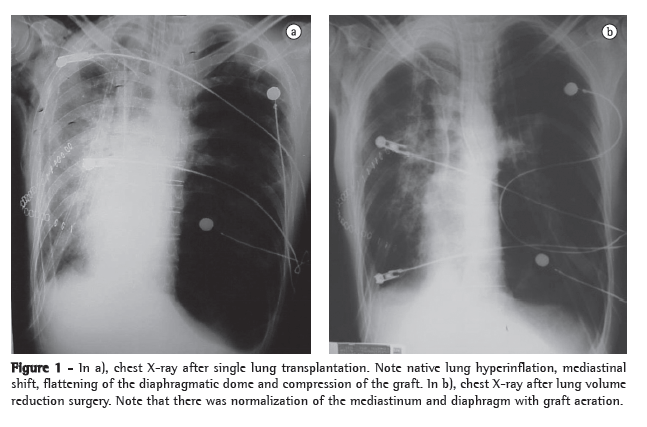

Three years after transplantation, there was progressive deterioration of pulmonary function, with clear signs of lung hyperinflation (FEV1, 69%; FVC, 71%; TLC, 136%; and RV, 278%). At the time, the patient experienced dyspnea on minimal exertion.

Reduction of native lung volume by means of left lower lobectomy was chosen because scintigraphy revealed lower perfusion in the left lung base (22%) than in the right lung base (78%). In addition, we considered the lower likelihood of prolonged air leak related to lobectomy. The patient underwent lobectomy. There was a favorable response and immediate improvement in the breathing pattern. Postoperative pulmonary function testing showed an FEV1 of 81%, FVC of 76%, TLC of 99% and RV of 150%. Four years after surgery, the patient was in good health and was fully able to perform his habitual activities (Figure 2).